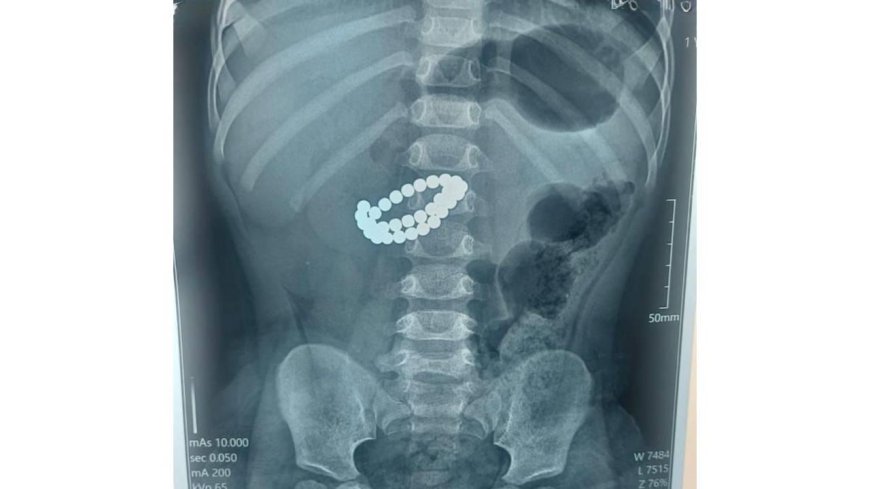

Алматыда екі жасар бала 31 магнит жұтып қойған

Балаларға шұғыл медициналық көмек көрсету орталығында 31 магнит жұтып қойған сәбиге шұғыл ота жасалды, деп хабарлайды Sadaq.kz.

Қоғамдық денсаулық сақтау басқармасының өкілдерінің хабарлауынша, қабылдау бөліміне 1 жас 9 айлық бала өте ауыр жағдайда жеткізілген. Тексеру нәтижесінде дәрігерлер "ішектегі бөгде заттар – 31 магнит, жіңішке ішектің көп жерден тесілуі, перитонит" диагнозын қойды.

Баланың өмірін сақтап қалудың жалғыз жолы – шұғыл хирургиялық ота жасау еді. Дәрігерлер ортаңғы лапаротомия жасап, құрсақ қуысы ағзаларына толық тексеру жүргізді. Ота барысында магниттер ішектен алынып, жіңішке ішектегі көптеген тесік тігілді, құрсақ қуысы тазартылып, дренаж орнатылды. Сонымен қатар ішекке трансаналдық интубация жасалды.

Орталық хирургі Асқар Ризвановтың айтуынша, магниттердің басты қаупі – олардың ағзаға бөлек-бөлек түскенімен, ішекте бір-біріне тартылып, ішек қабырғасын қысып қалуында екен.